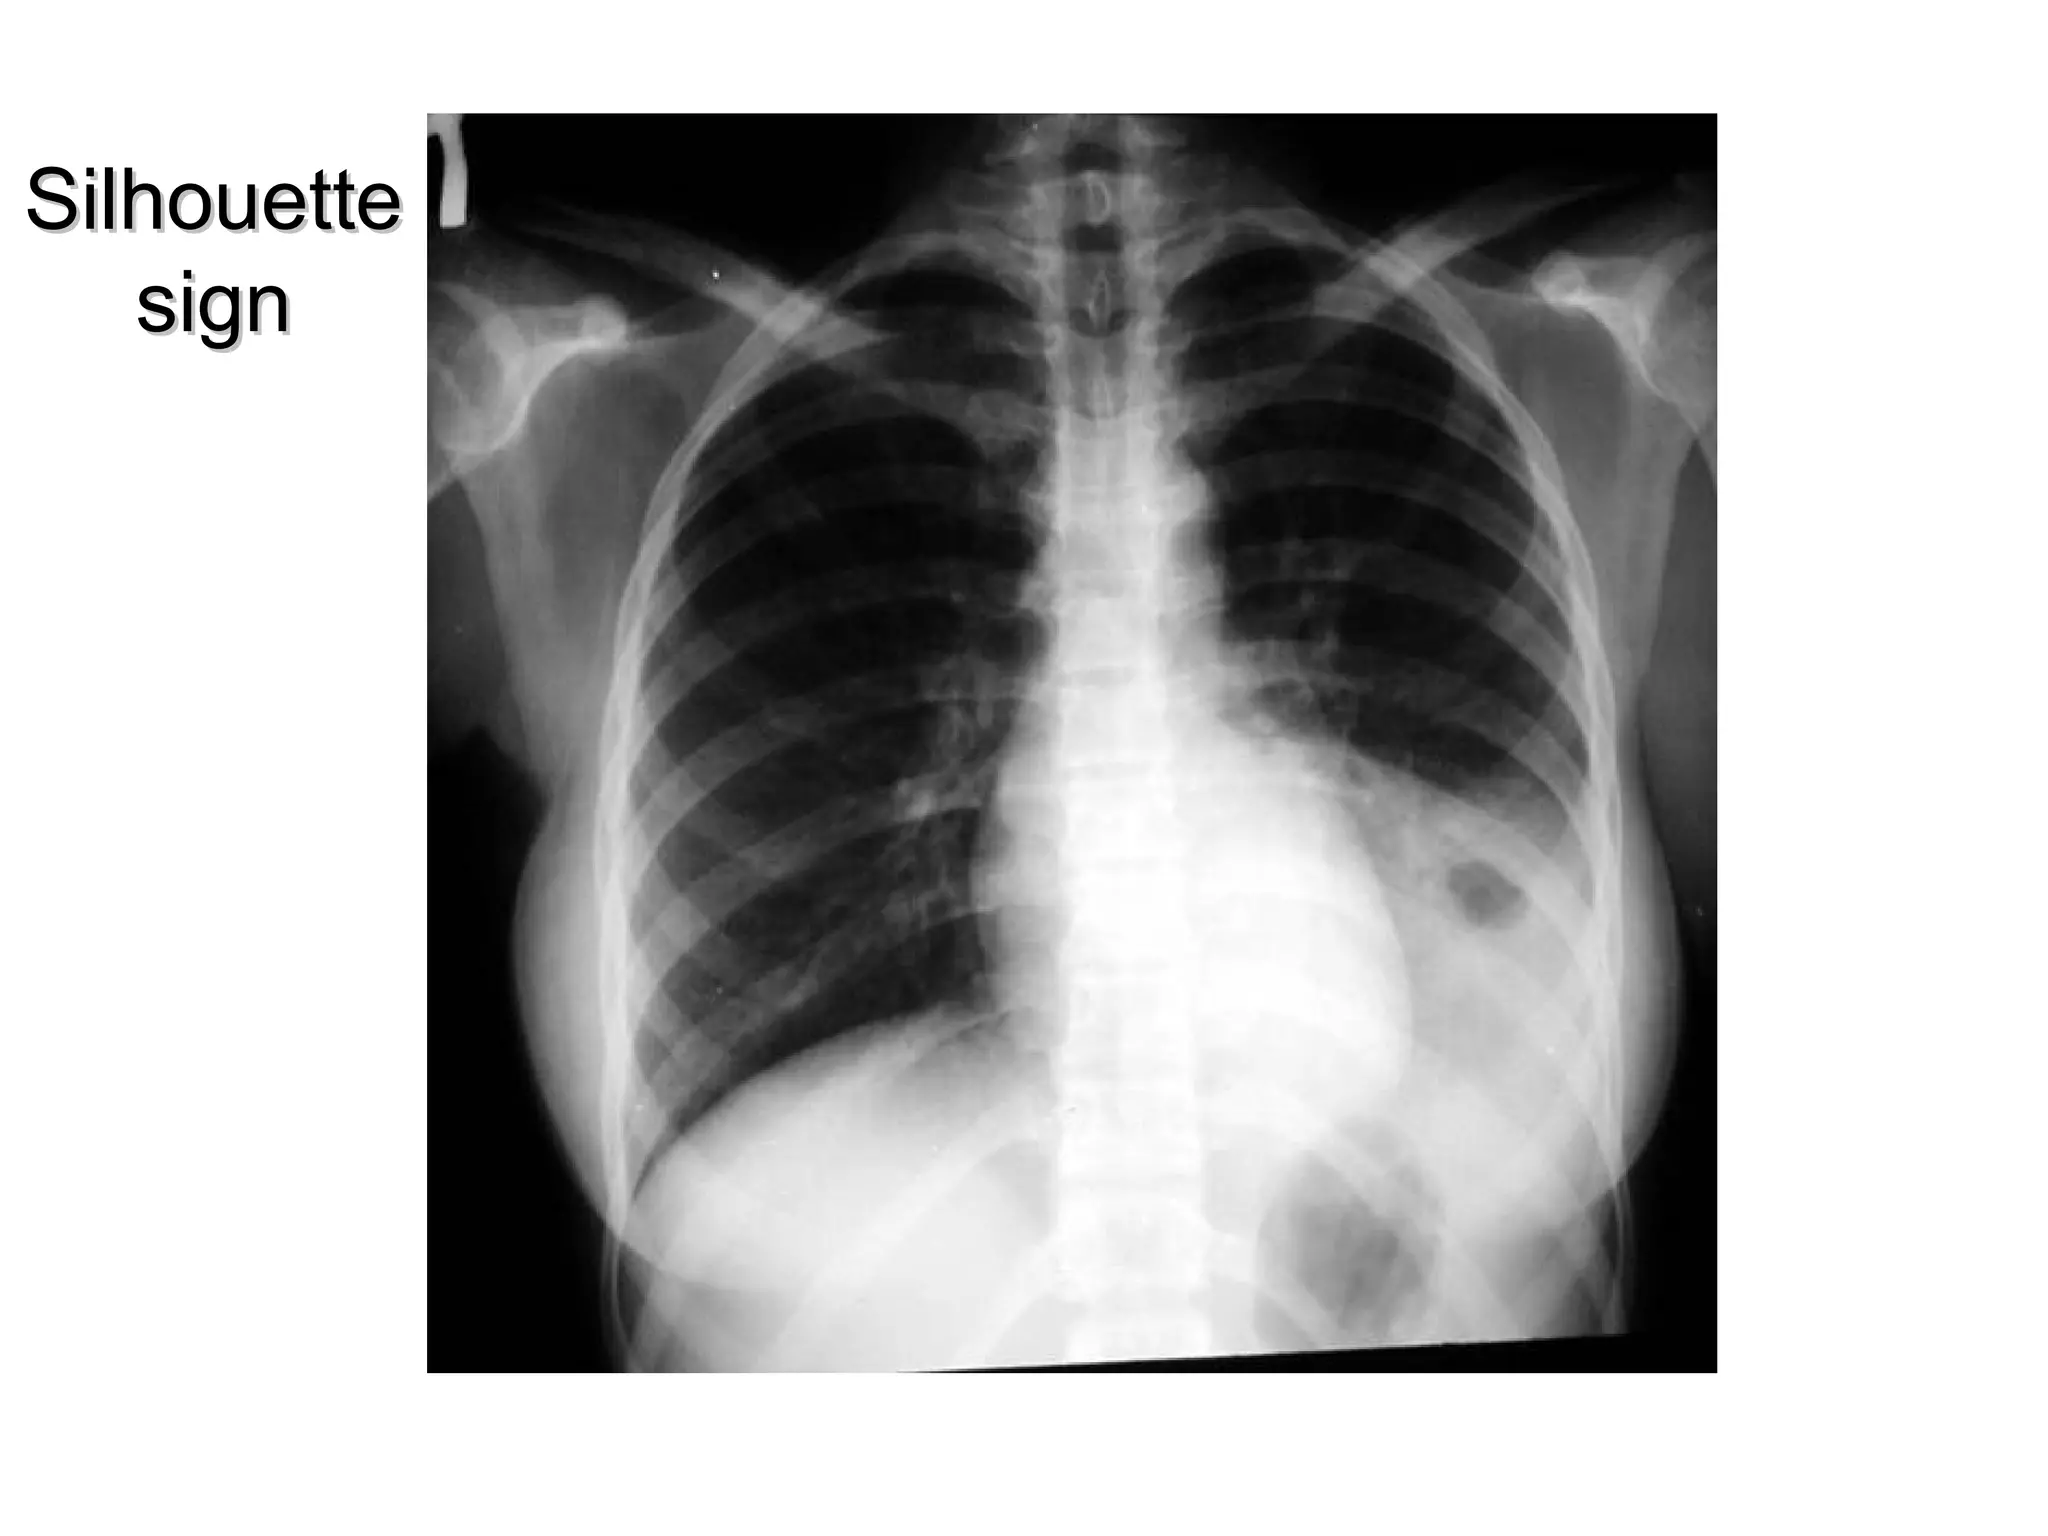

The silhouette sign is the loss of an interface

by adjacent disease, when air in the

alveolar space is replaced by fluid or soft

tissue, there is no longer a difference in

radiodensity between that part of the lung

and the adjacent structures. Therfore the

silhouette is lost and the silhouette sign is

present.

Interpretation of abnormalfilm • Radiological signs The silhouette sign is the loss of an interface by adjacent disease, when air in the alveolar space is replaced by fluid or soft tissue, there is no longer a difference in radiodensity between that part of the lung and the adjacent structures. Therfore the silhouette is lost and the silhouette sign is present.